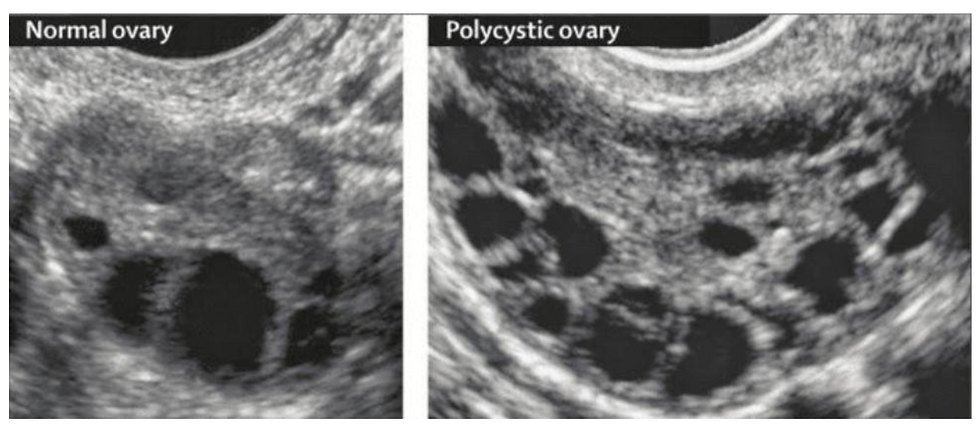

ovare cu aspect polichistic la ecografie

Aspect ecografic polichistic

sursă imagine: https://www.drmoomjy.com/blog/pcos